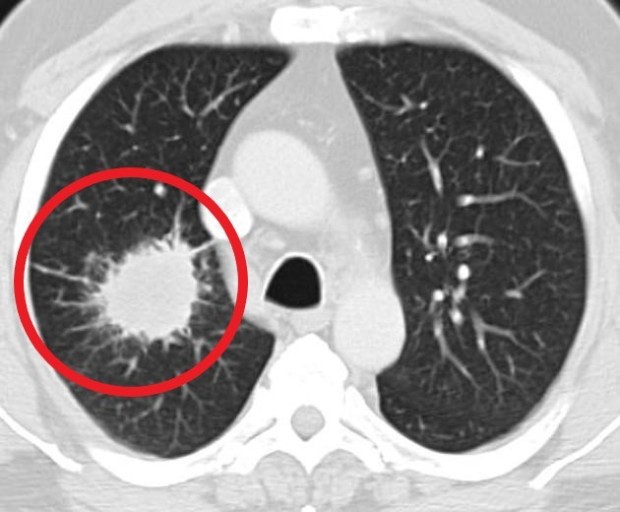

폐렴 증상을 겪는 그럴 경우 X선 촬영 및 배양 검사로 진단할 수 있어요. 필요에 따라 소변, 혈액, 혈청 검사, CT 등을 추가로 실시해요. 폐렴 진단을 받은 환자는 일반적으로 입원을 권장하지 않지만 젊거나 기초질병이나 호흡곤란이 심한 그럴 경우, 고령, 임신 등의 그럴 경우 전문기관에 방문해서 상황에 맞는 신속한 치료와 상태 개선, 위험예방을 받는 것이 좋아요. 폐렴 증상의 치료에서 가장 주요한 것은 항생제로 원인균을 제거하는 것인데요. 세균이나 바이러스 감염에 의해 발생하며 처음에는 항바이러스제를 통해 감기처럼 치료하기도 해요.